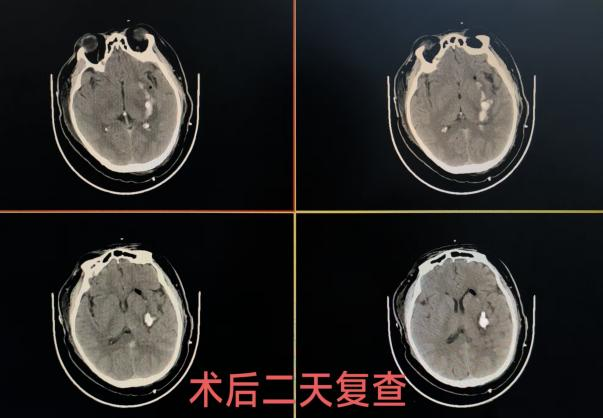

手术由神经外科团队操作,过程顺利,仅用时45分钟。术后复查头部CT显示,颅内血肿较术前已显著减少,引流管位置精准满意。术后辅以尿激酶冲管治疗,两天后再次复查CT,左侧基底节区血肿已基本清除干净,患者顺利拔除引流管,标志着本次微创干预取得圆满成功。